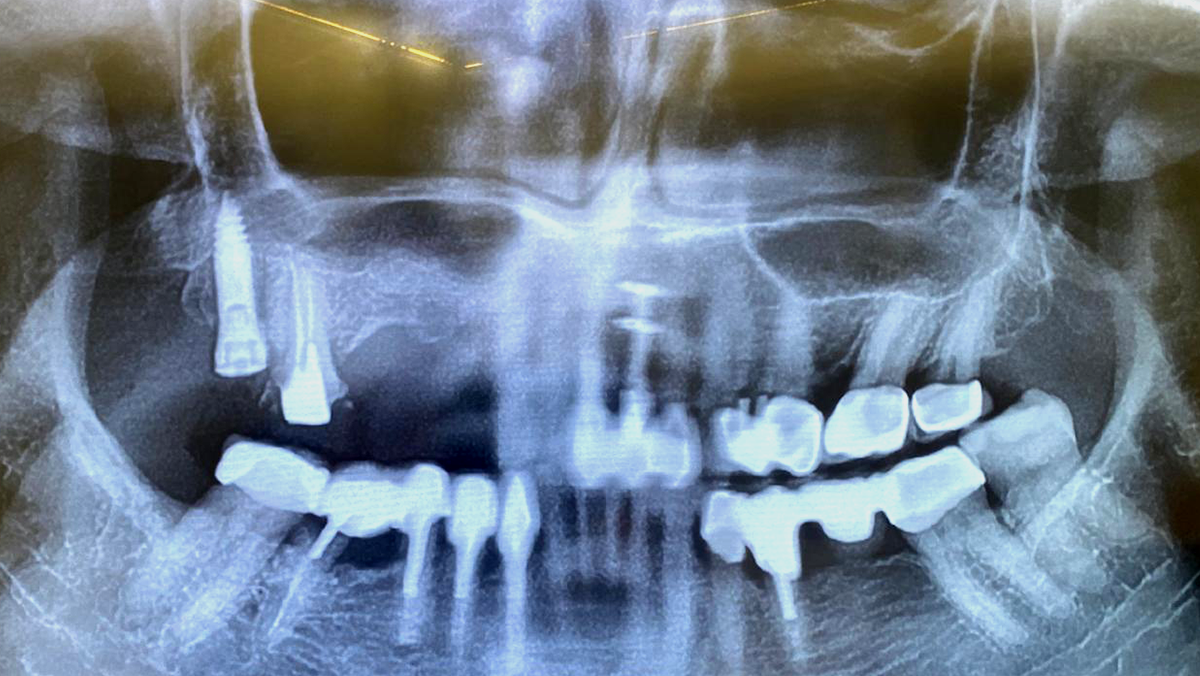

une chirurgie en direct commentée par le Dr Gérard Scortecci, réalisée dans le secteur postérieur maxillaire droit

Pour cette patiente ukrainienne, une activation ostéogénique avait été effectuée 45 jours avant la chirurgie, optimisant ainsi le potentiel biologique local pour la pose des implants.

De plus, la réhabilitation a été minutieusement préparée en amont grâce à une planification numérique complète et à l’assistance de l’intelligence artificielle.

Un bridge provisoire, conçu et imprimé numériquement avant l’intervention, a été planifié pour être ancré sur la 17 et prendre appui sur les faces palatines des 12 et 13.

La planification numérique consiste à préparer toute l’intervention à l’aide d’outils digitaux afin de visualiser l’anatomie du patient, et de choisir l’emplacement exact. Cette approche a permis d’anticiper les contraintes anatomiques et d’optimiser le futur projet prothétique avant même l’intervention.

AVANT